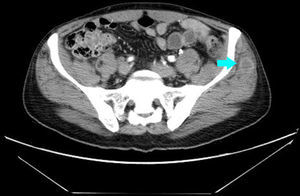

Varón de 56 años, fumador de 40 paquetes/año, que acude a la consulta por presentar dolor a nivel del musculo trapecio derecho, después de un partido de tenis. Entre sus antecedentes personales destaca un infarto de miocardio inferior 15 años antes, a tratamiento con simvastatina 10mg, AAS 100mg y atenolol 50mg. A la exploración se palpaba una discreta tumefacción dolorosa en el músculo trapecio. El cuadro es interpretado inicialmente como una contractura muscular tratándolo con AINE, relajantes musculares y fisioterapia. Un mes más tarde acude nuevamente a la consulta por astenia y empeoramiento del dolor que se había extendido a la musculatura pelviana y antebrazo derecho. No refería cefalea, tos, disnea ni fiebre. En la analítica destaca una VSG de 70 y PCR 4. Se realiza una radiografía de tórax donde se aprecia una masa parahiliar derecha. El TAC torácico y abdominal evidencio una masa hiliar derecha de 5,5cm y múltiples metástasis musculares, al menos en el subescapular derecho (fig. 1), psoas izquierdo, recto anterior izquierdo y musculatura glútea (fig. 2).